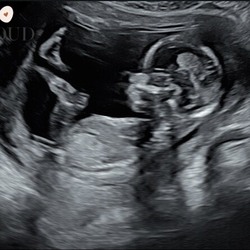

Kleine update: vandaag langs geweest voor de echo en… een kloppend hartje gezien 🥹🤍Zo dankbaar en opgelucht. Eén stapje tegelijk 🤍

6 weken! De vorige keer zagen we dat de baby al was gestopt met 5 weken zonder hartje dus dit keer wel een hartje zien kloppen wel een heel fijn gevoel ☺️🤍